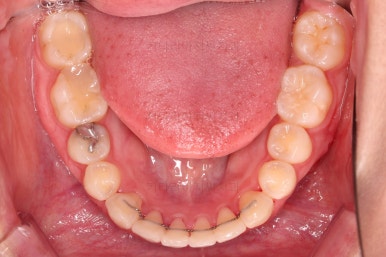

틈새는 거의 다 붙어가는데 교합이나 중앙선 등을 위해 추가적으로 밀고 당기기를 해줍니다.

디테일을 좀 더 맞추고 부산치아교정 마무리를 합니다.

치아 갯수 및 사이즈 문제로 위아래의 정중선은 100% 일치시키긴 힘들지만 가능한 선에서 최대한 맞추었고요.

윗니가 1개 없는 상태에서의 교합도 잘 맞추고 마무리를 했습니다.

다시 틈새가 벌어지지 말라고 유지철사를 붙여주었고요.

전후 비교해 볼게요.

임플란트 하러 오신 분을 임플란트 없이 마무리 했고요.

젊으신 나이에 임플란트를 하기 보다는 약간의 시간을 더 투자해서 이렇게 마무리를 하는게 여러모로 합리적인 치료였습니다.